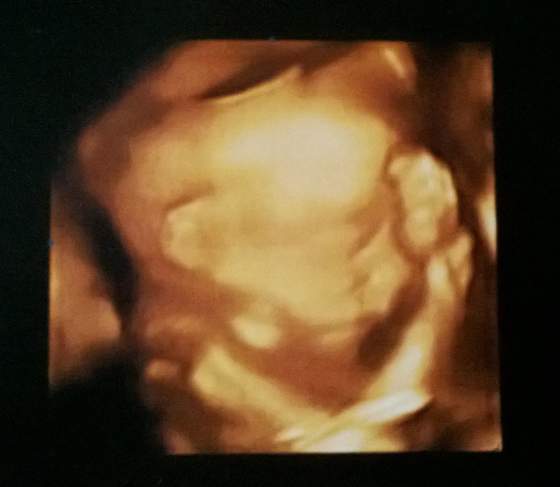

21+3 - taki obrażony :-p